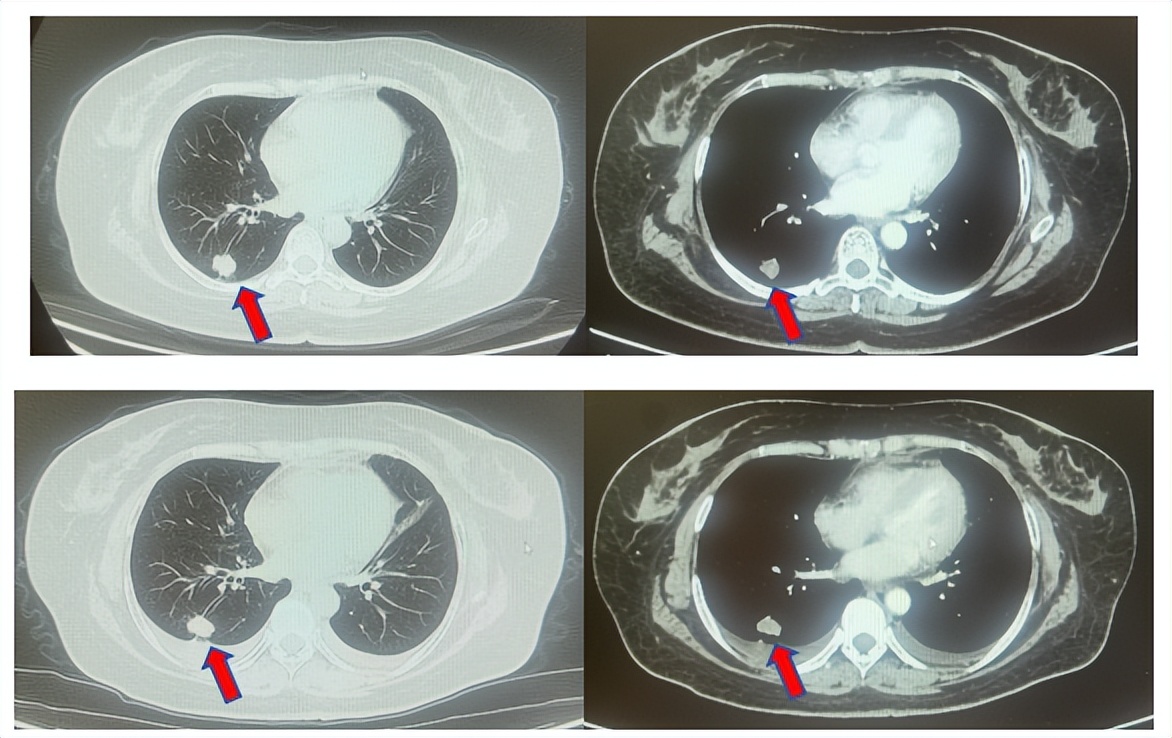

1.2影像学检查(图1)

肺+全腹CT:右肺下叶占位、伴纵隔多发淋巴结肿大,恶性可能性大;右侧心膈角结节,左侧胸廓入口淋巴结增大。

脑MRI:左侧顶叶及右侧小脑结节,转移可能性大。

图1:上两图分别展示基线肺CT肺窗及纵隔窗影像,下三图表示脑MRI影像。红色箭头指示病灶位置,分别为右肺肿物、右侧肺门转移病灶、左侧顶叶病灶、右侧小脑病灶及冠状面上的颅内两个病灶。